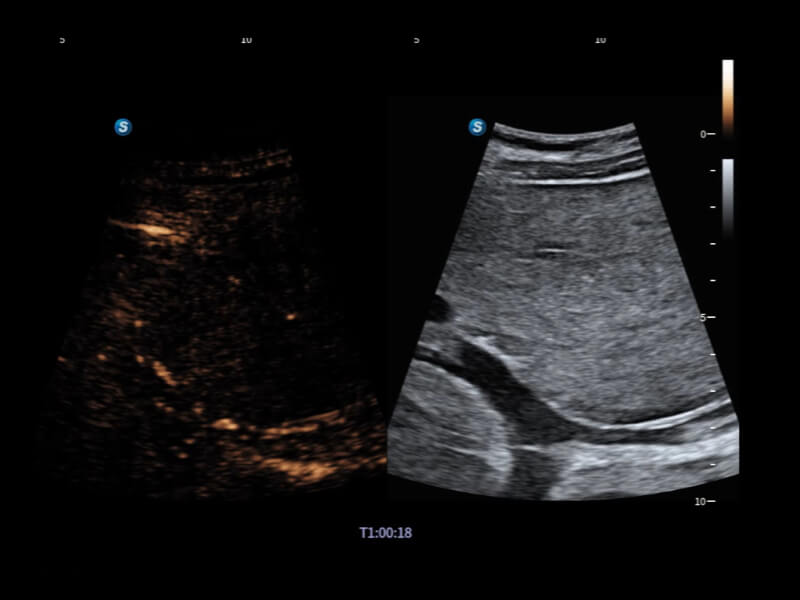

丰富的血流动力学检测技术,可在不同医疗场景中高效捕捉血流信号,助力临床诊疗。

在传统血流的基础上优化扫查和算法策略,能够更好的抑制组织信息,提炼红细胞运动信息,得到更高帧频,高灵敏度和分辨率的血流信号,还原更真实的血流动力学。

通过光照模型,使二维血流显示出立体的效果,增加血流的敏感性、成束性,减少外溢。可以和其他不同的血流技术联合使用,融合不同技术的优势。轻松应对微小血管,增强血流的立体效果,提升视觉敏感性。